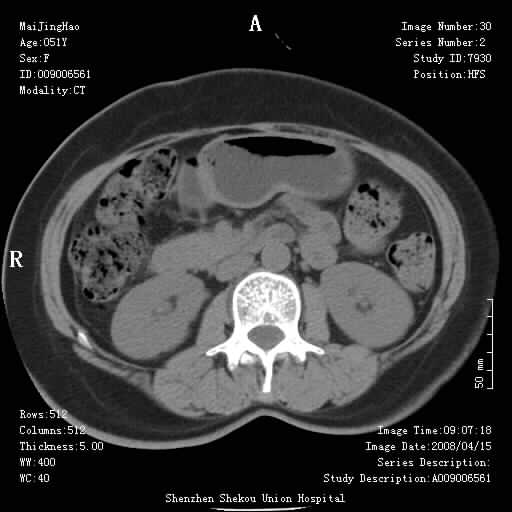

以下是引用余辉在2008-4-26 8:55:00的发言:[br]患者有结石史,此次腹痛4小时,胆总管全程扩张,应有胆总管末端梗阻,此次仍考虑胆结石症,积气不外两种原因,一种是结石下移时肠道内气体逸入,其次为产气菌感染。(倒数第三幅图像于扩张之胆总管末端似可见稍高密度影,考虑为结石影)

以下是引用yangyudong333在2008-4-26 6:17:00的发言:[br]1胆系感染,可能为金葡菌感染,2考虑有化脓性胆管炎致胆总管扩张,3胰头部增大,建议做增强

以下是引用听蝉观竹在2008-4-26 11:41:00的发言:[br]胆道手术分两种情况:[br]1、如果仅仅做胆囊切除手术,肝内胆管不会积气,只会出现胆总管代偿扩张,因为奥迪氏括约肌依然功能正常胆道与外界并不相通;[br][br]2、胆囊切除+胆总管空肠吻合手术(即roux-y式),则肝内胆管会出现积气,只是因为胆管与小肠相通,气体来源于小肠。这是临床十分常见的手术。[br][br]这个病例应该是胆囊切除+胆总管空肠吻合手术,是正常手术后表现,并不是胆道感染的表现。

以下是引用liangshusheng在2008-4-26 12:34:00的发言:[br]11年前做的手术现在还有积气,可能吗?还是考虑有胆管炎产气,胰头部增大,建议做增强